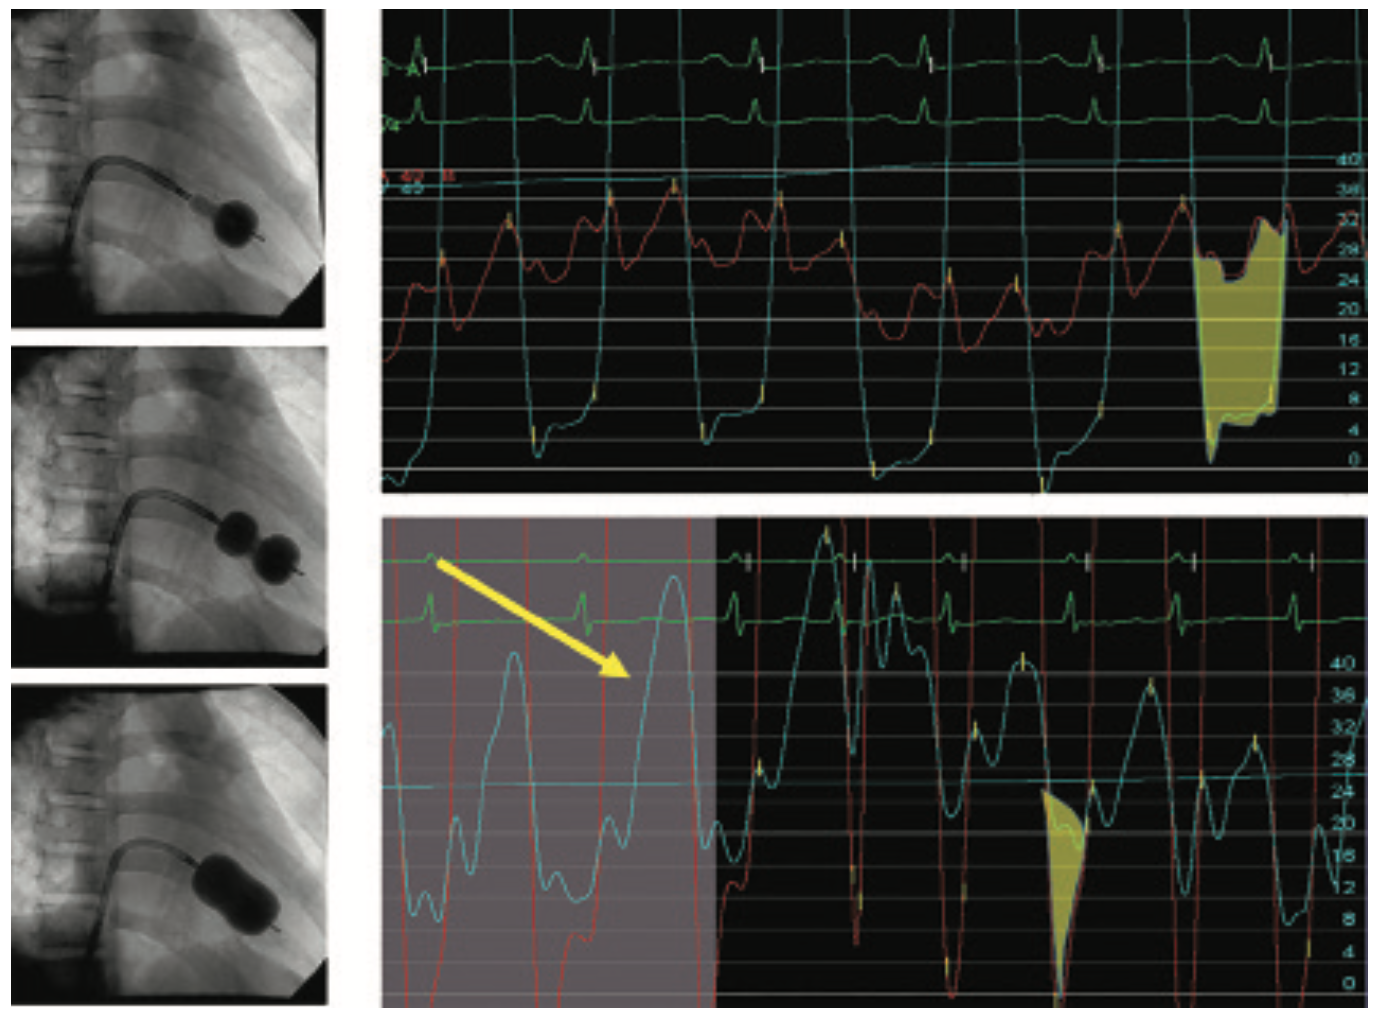

In another case illustrating tamponade after an LV gram or during a percutaneous coronary intervention (PCI) with wire perforation, the arterial pressure tracing (Figure 4) shows a narrowed pulse pressure, tachycardia, and large differences in systolic pressure variation between inspiration and expiration (pulsus paradoxus), typical hemodynamic findings for pericardial tamponade. Noting such a pressure, the operators should prepare to perform immediate pericardiocentesis, begin fluid resuscitation, and notify the operating room as the situation requires. An in-lab echo is very helpful in identifying the fluid and assisting in the pericardiocentesis. Figure 5 shows echocardiographic frames of the effusion, bubble contrast during pericardiocentesis image, and a post-cath evacuation of the pericardial fluid.

The hemodynamics before pericardiocentesis show arterial pressure pulsus paradoxus with a mean arterial pressure of 110 mmHg (Figure 6). The middle frame shows elevated right atrial and pericardial pressures. In this case, although RA/pericardial pressures are not identical, the blunted pressure waveforms and near-mean equalization at around 22 mmHg are consistent with the echo findings. After pericardiocentesis, arterial pulse pressure and respiratory variations have resolved with an increase in mean arterial pressure and decrease in RA pressure. The final RA pressure at 12 mmHg suggests some effusive-constrictive pericardiocentesis remains.